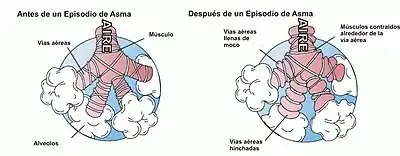

El origen de la enfermedad es complejo e involucra la inflamación, la obstrucción intermitente y la hiperreactividad (incremento en la respuesta broncoconstrictora) de las vías respiratorias. La presencia de edema y secreción de mucosidad contribuye tanto con la obstrucción como con el aumento de reactividad. La enfermedad puede tener un curso agudo, subagudo o crónico, dependiendo de la frecuencia, duración e intensidad de sus manifestaciones clínicas.[5]

Los síntomas del asma son la respiración sibilante, la falta de aire, la opresión en el pecho y la tos improductiva durante la noche o temprano en la mañana.[10] Estos síntomas se dan con distinta frecuencia e intensidad, intercalándose períodos asintomáticos donde la mayoría de los pacientes se sienten bien. Por el contrario, cuando los síntomas del asma se exacerban, se produce una crisis de asma. Puede ser una crisis respiratoria de corta duración, o prolongarse con ataques asmáticos diarios que pueden persistir por varias semanas. En una crisis grave, las vías respiratorias pueden cerrarse impidiendo que los pulmones realicen su función de intercambio gaseoso (recibir oxígeno y expulsar el dióxido de carbono) al punto que los órganos vitales tampoco puedan funcionar. En esos casos, la crisis asmática puede provocar la muerte.[11]

Obstrucción intermitente al flujo aéreo

La obstrucción al flujo aéreo se produce por varios factores: broncoconstricción aguda, edema de la vía aérea, formación de tapones mucosos crónicos y remodelamiento de la vía aérea. La broncoconstricción se produce por la liberación de mediadores dependientes de la inmunoglobulina E al exponerse a un alergeno aéreo y es el primer componente de la respuesta asmática temprana. El edema se produce entre 6 a 24 horas después del contacto con el alergeno, y su aparición se corresponde con la respuesta asmática tardía. La formación de tapones mucosos ocurre por la acumulación de exudado rico en proteínas y residuos celulares, y toma semanas en desarrollarse. La remodelación de la vía aérea se asocia con cambios estructurales del árbol bronquial debido a la inflamación mantenida en el tiempo y afecta en forma muy importante la reversibilidad de la obstrucción.[31]

- Fase temprana. Tiene lugar como reacción de los mecanismos inmunológicos o no inmunológicos frente a agentes alergenos, microbianos, etc. y se caracteriza por constricción de la luz (abertura en el conducto) de los bronquiolos.

- Fase tardía. Sobreviene al persistir el estado de crisis y constituye una acentuación de la misma caracterizada por edema e hiperreactividad bronquial, es decir, una fácil predisposición a la broncoconstricción.

- Fase crónica. Tiene lugar cuando el estado anterior no disminuye después del tratamiento habitual y, con frecuencia, la tos, acentúa la irritación bronquial. Ello conlleva a daño del revestimiento epitelial del bronquio, persistencia de la hiperreactividad bronquial y de moco bloqueante de las vías aéreas.